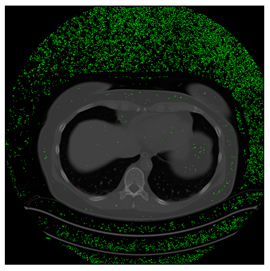

Table 5. Testing results of the Lung-PET-CT-Dx database.

Computers 10 00152 i031 Computers 10 00152 i032 Computers 10 00152 i033

BPP0.05PSNR61.49Modified BPP0.046